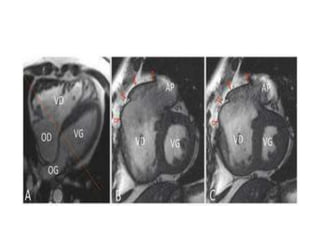

IRM

• Gold standard pour suivi  indication de

revalvulation

• Objectifs :

– Évaluation masse, fonction, volumes VG et VD

– Quantification IP, IT, Qp/Qs

– Anomalies cinétique segmentaire, recherche viabilité

myocardique (zones cicatricielles)

– Anatomie de la voie droite, AP tronc et branches

– Évaluation aorte, valve aortique, coronaires

– Recherche de shunt intra- ou extra-cardiaque

 Varient en fonction de l’âge du patient

IRM • Gold standardpour suivi  indication de revalvulation • Objectifs : – Évaluation masse, fonction, volumes VG et VD – Quantification IP, IT, Qp/Qs – Anomalies cinétique segmentaire, recherche viabilité myocardique (zones cicatricielles) – Anatomie de la voie droite, AP tronc et branches – Évaluation aorte, valve aortique, coronaires – Recherche de shunt intra- ou extra-cardiaque  Varient en fonction de l’âge du patient